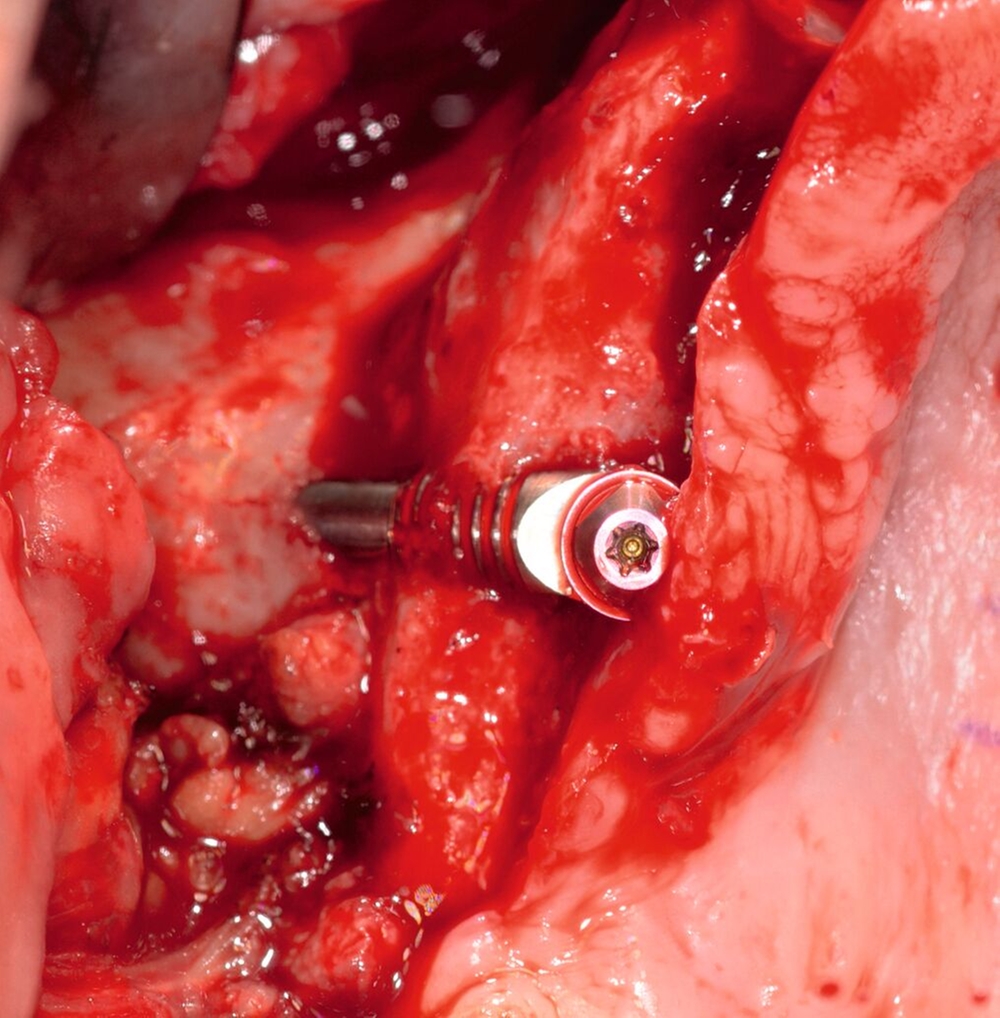

Die Erstbeschreibung von Zygoma-Implantaten — also von langen Implantaten, die ins Jochbein inseriert werden — stammt aus den 1980er-Jahren. Hier wurden sie bei Patienten nach Maxillektomien zur Wiederherstellung von Funktion und Ästhetik eingesetzt (Abbildungen 1 und 2).

Das Protokoll für die Platzierung eines Zygoma-Implantats beginnt mit der Osteotomie auf dem Alveolarkamm des Oberkiefers in der Position des zweiten Prämolaren beziehungsweise des ersten Molaren. Die Bohrung verläuft an der Innen- oder Außenseite der Kieferhöhle (abhängig vom Grad der Konkavität der seitlichen Kieferhöhlenwand) und durchdringt den Körper des Jochbeinknochens, wodurch der apikale Teil des Implantats im Jochbeinkörper verankert werden kann [Bedrossian, 2021] (Abbildung 8).

Die Zygoma-Implantate sind daher – bei ausreichendem Knochen im Alveolarkammbereich – quadkortikal stabilisiert. Die erste bikortikale Stabilisierung befindet sich am Oberkieferalveolarkamm und die zweite bikortikale Stabilisierung im Jochbeinkörper [Bedrossian et al., 2006].